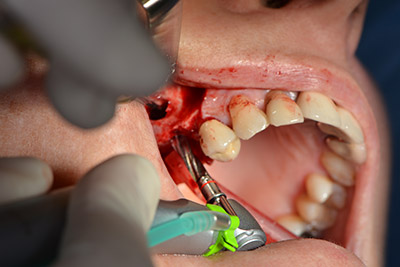

Die anschließenden Bohrungen werden mit einer reduzierten Umdrehungszahl von 300/min durchgeführt. Hier zeigt sich einer der Vorteile der Implantmed. Das chirurgische Protokoll kann voreingestellt werden – die einzelnen Positionen sind über einen einfachen Druck auf die Position „P“ der Fußsteuerung anwählbar. (Abb. 10 bis 11)

Die nächste programmierte Position ist bereits die Implantateinbringung und in unserem Hause mit einer Kraft von 32 Ncm voreingestellt (Abb. 12).

Im nächsten Schritt wird die Sinusbodenelevation mit simultaner Implantation durchgeführt. Für die bukkale Fensterung der Kieferhöhlenwand gibt es auch hier bei der Implantmed an der ersten Position eine Voreinstellung.

Mit 35.000/min wird das Fenster angelegt und anschließend die Schneidersche Membran nach kranial präpariert. (Abb. 13 bis 14).